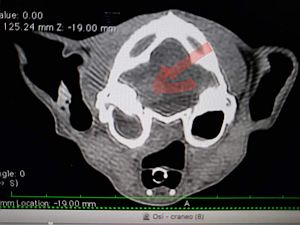

Osi kam im Juni als absoluter Notfall in die Obhut der Tierschützer. Ihr Zustand war katastrophal, sie war schon komatös, hatte motorische Ausfälle und eine Kopfschiefhaltung. Nebenbei wurde auch noch eine Nackenverletzung unbekannter Herkunft gefunden. Sobald sie einigermaßen stabilisiert war, wurde ein MRT gemacht. Es zeigte sich eine Masse in der hinteren Schädelgrube, die Druck auf den linken Kleinhirnlappen ausübte, so dass die Tierärzte von einem Lymphom oder einem Meningeom ausgingen. Außerdem wurde Sekret in den Paukenhöhlen der Ohren gefunden und eine bilaterale Otitis des linken Ohres als wahrscheinliche Diagnose vermutet.

Osi hat eine schlimme Zeit hinter sich, aber dank der monatelangen Behandlung durch die Tierärzte, hat sie sich soweit erholt, dass sie nun endlich aus der Klinik entlassen werden konnte und in die Auffangstation der Tierschützer umziehen konnte. Die Masse im Kleinhirn hat sich verringert, was prima Nachrichten sind.